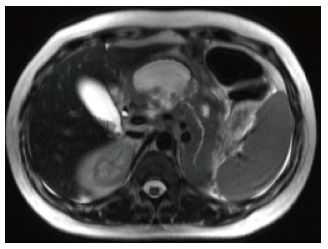

Изображение 4. 55-летний мужчина после удара бейсбольной битой по животу. На МСКТ-снимке (А) обнаружена большая рваная рана головки поджелудочной железы (стрелка), затрагивающая более 50 % толщины паренхимы и указывающая на высокую вероятность повреждения протока.

На магнитно-резонансной холангиопанкреатографии (В) у того же пациента подтверждается повреждение протока (стрелка).

Изображение 5. Разрыв поджелудочной железы IV степени у 41-летнего мужчины, пострадавшего в результате ДТП. На МСКТ (А) показан линейный разрыв (стрелка) в головке поджелудочной железы справа от верхней брыжеечной вены.

На МРТ (В) изображение того же пациента демонстрирует разрыв в головке поджелудочной железы (стрелка).